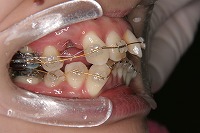

26歳1か月

右

左

前歯が出ていて歯並びが悪い事を主訴に来院された、26歳1か月の女性です。診断「歯と歯槽基底の大きさの不調和による叢生」上顎は右側第1小臼歯と左側の犬歯、下顎は抜歯をせず治療を行いました。